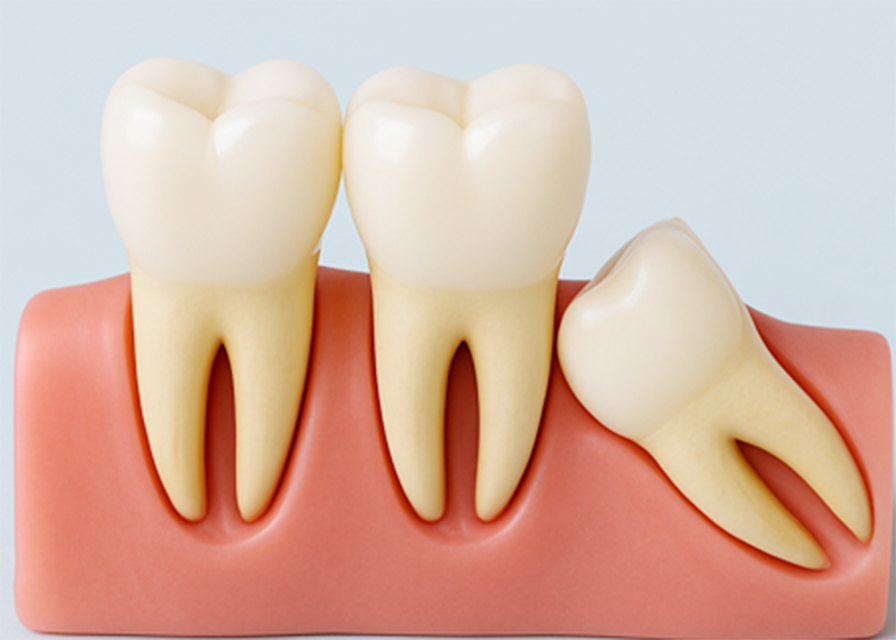

「親知らず」という言葉は皆さん聞いたことがあるかと思います。「一番奥に生えている歯」というイメージがあるかもしれませんが、誰でもそれに当てはまるわけではありません。たしかに、親知らずは永久歯の中で一番最後に生える歯で、通常は上下の顎の左右に計4本あります。しかし、もともと親知らずがない方がいたり、4本すべて生えてこないという方もいたりします。生える年齢としては、永久歯が15歳くらいで揃うのに対し、親知らずは20代ごろに現れます。

親知らずが問題とされるのは、主に正常に真っ直ぐ生えてこないケースです。少し傾いて隣の歯に当たったり、真横に生えて隣の歯を押し出すような状態になったりすることがあります。また、歯肉に埋もれる形で横向きに生えることもあります。親知らずが正常でない向きに生えると、歯磨きがいき渡らず汚れがたまります。すると、歯肉の炎症や虫歯・歯周病を引き起こしやすくなり、親知らずが痛みます。また、隣の歯の虫歯や歯周病の原因となることもあります。